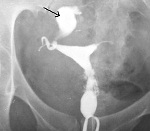

• Гистеросальпингография. При постоянном варианте болезни контрастное вещество не поступает в одну или обе трубы и скапливается в матке. При вентильном сактосальпинксе пораженная труба определяется как расширенная, колбообразная.